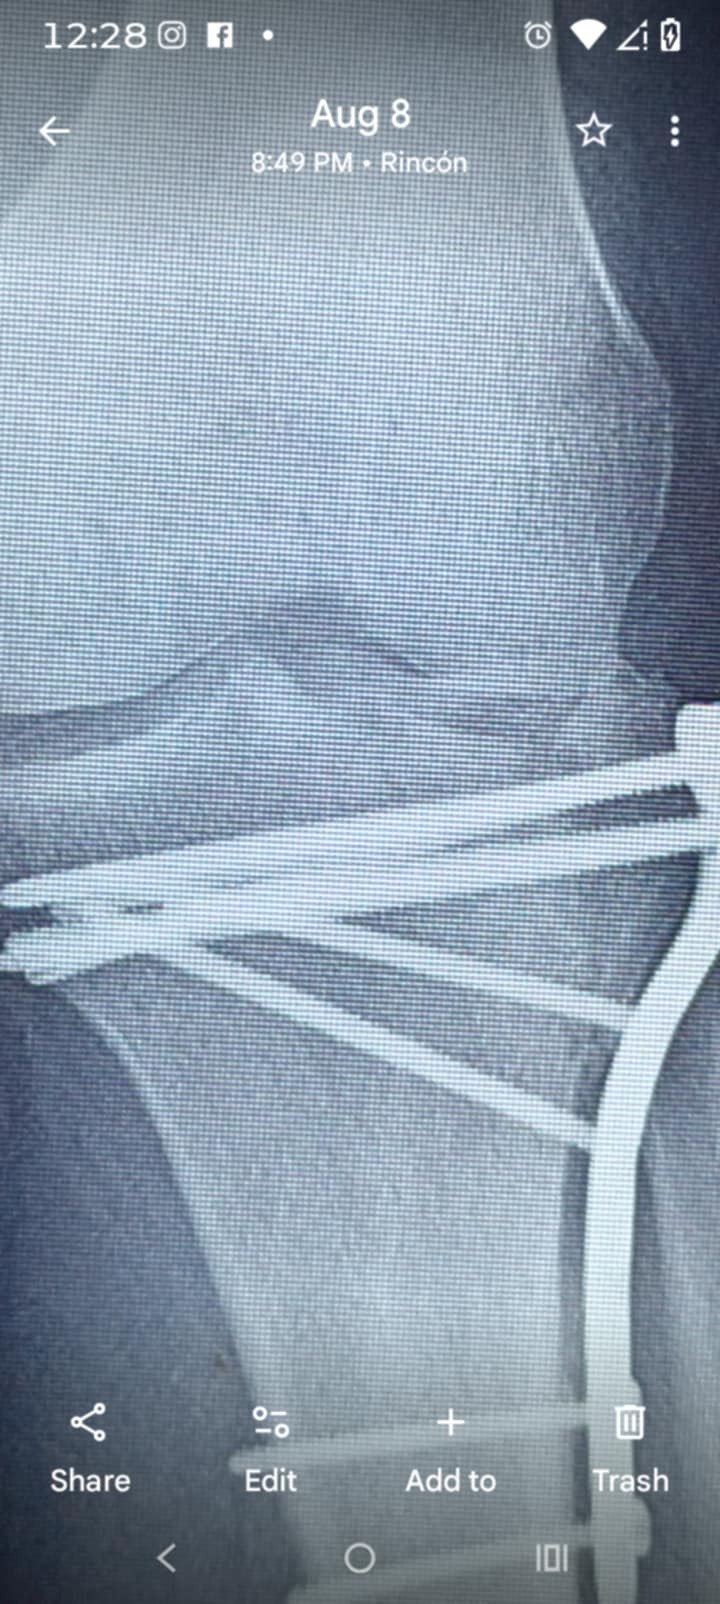

On September 15, 2024, I suffered a serious injury and broke my tibia. Since that day, my life has been turned upside down. I’ve been unable to work and do the things I normally take pride in—providing for myself and my family.

I’ve done my best to stay strong and push through this difficult time, but the reality is that recovery has been longer and more challenging than I ever expected. Now, I am facing surgery scheduled for April 23, and with it comes medical expenses that I am simply not able to handle on my own.